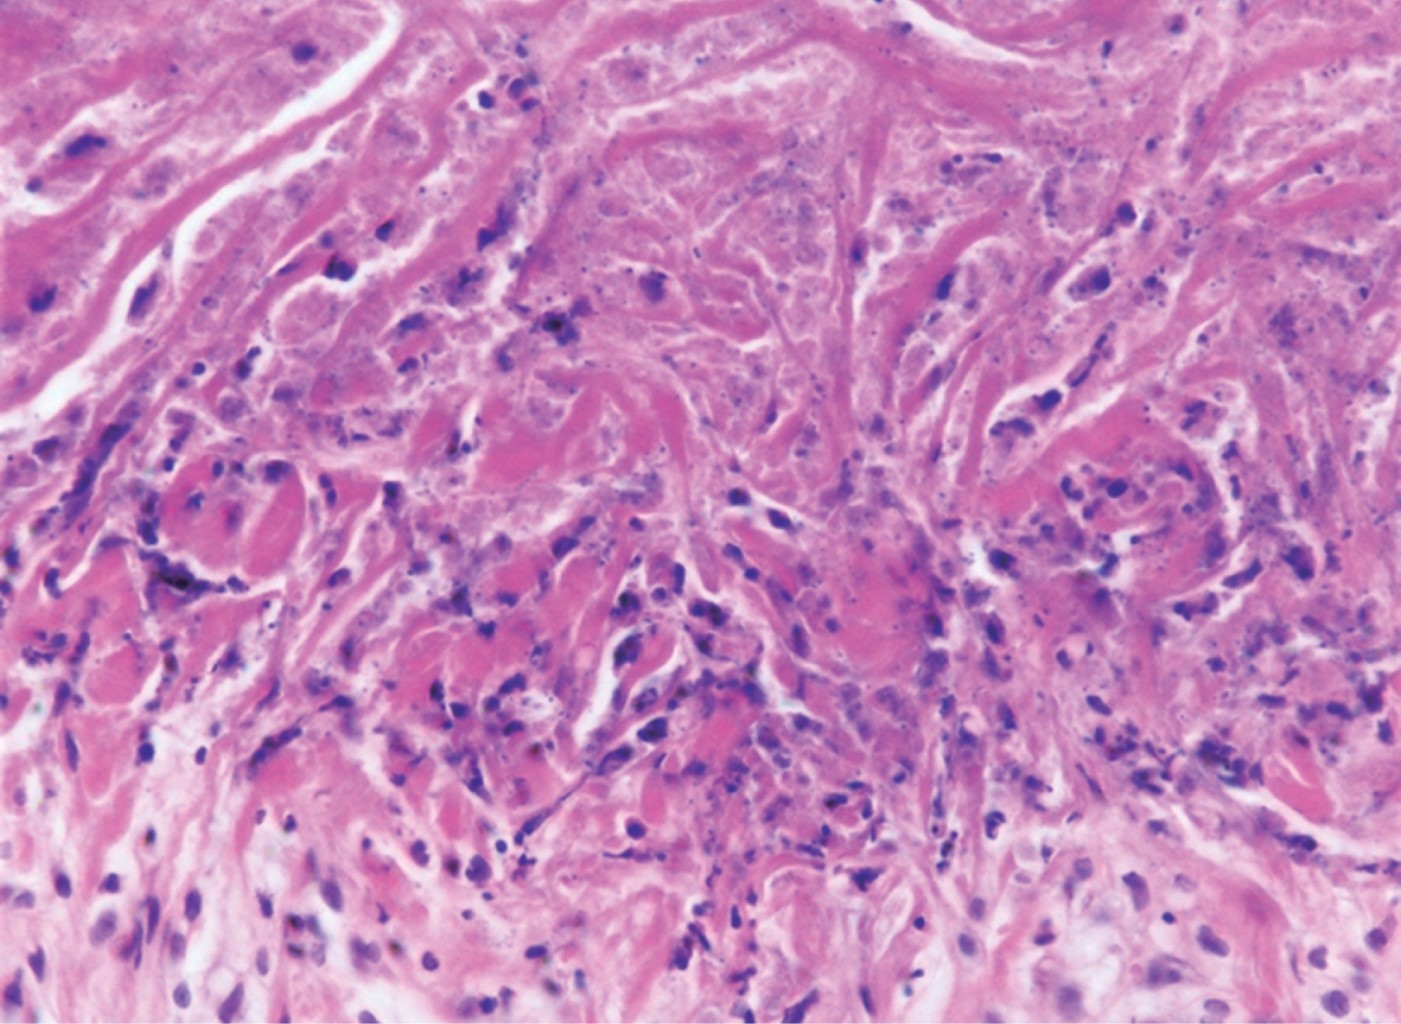

Perforating dermatoses are a group of diseases clinically characterized by the transepidermal removal of various skin materials. In secondary perforating dermatoses perforation and removal of connective tissue fibers is an occasional phenomenon, occurring in conjunction with other chronic dermatoses, such as necrobiosis lipoidica (NL). The perforating variety (PNL) is even less frequent, with few cases reported in the literature. Diabetes mellitus 2 (DM2) is associated in 90-100%. Definitive diagnosis can only be made by clinical-histopathological correlation. Histopathology shows elimination of necrobiotic material through the follicular canal, in addition to "palisade" granulomas with collagen necrobiosis. The disease has a chronic course with a tendency to scarring, ulceration and in some cases progression to carcinomas. The treatment of NL and PNL is difficult, due to the rarity of the disease and lack of clinical trials. In this article we present the case of a 63-year-old male patient with perforating necrobiosis lipoidica with recently diagnosed DM2.

Figure 1

Figure 2

Figure 3

Figure 4

Figure 5